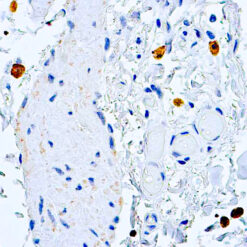

This MAb recognizes human 17-26kDa protein, which is identified as cytokine TNF-α (Tumor Necrosis Factor-alpha). Monomeric human TNF-α is a 157 amino acid protein (non-glycosylated) with a reported molecular weight of 17 kDa and can be expressed as a free molecule, also TNF-α is generated as a precursor form called transmembrane TNF-α can be expressed as a cell surface type II polypeptide consisting of 233 amino acid residues molecular weight 26 kDa. TNF-α is an important cell-signaling component of the immune system. It is a protein secreted by LPS stimulated macrophages, and causes tumor necrosis when injected into tumor bearing mice. TNF-α is currently being evaluated in treatment of certain cancers and AIDS Related Complex.

| Cellular Localization | Cytoplasmic and extracellular (secreted) |

| Positive Control Tissue | Colon, Histiocytoma, Pancreas |